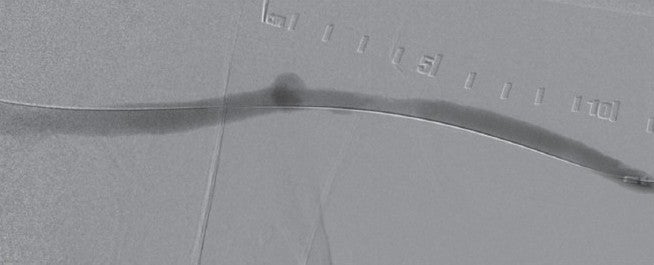

バイアバーン® ステントグラフトの展開は容易であったが、後拡張前の残存狭窄部分は造影時のデバイス形状から確認できた(図3)。バイアバーン® ステントグラフトの展開にあたっては柔らかいガイドワイヤーではデバイスのカテーテルが屈曲し展開が困難になる場合もあるので、硬質のガイドワイヤーを用いることが重要不可欠となる。